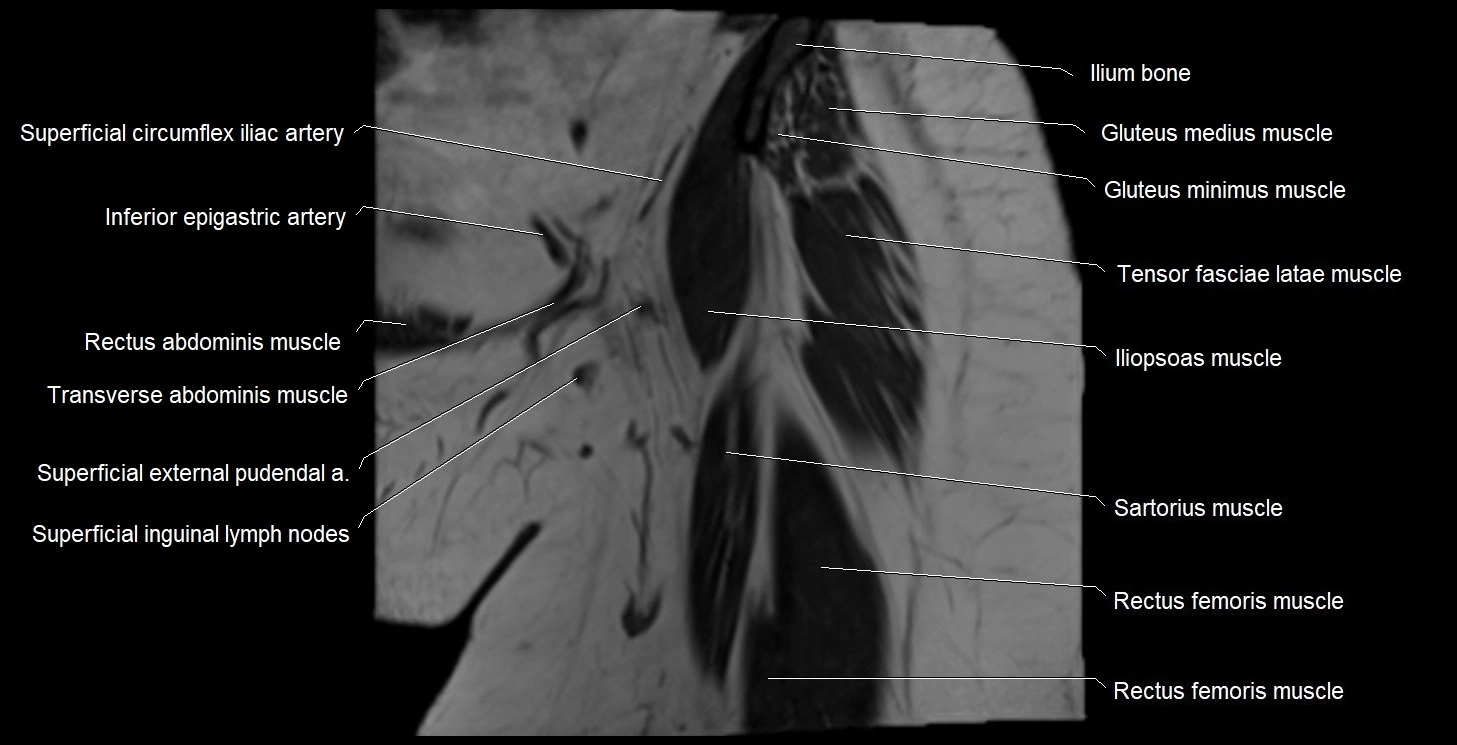

- Anterior superior iliac spine

- Deep circumflex iliac artery

- Femoral nerve

- Gluteus medius muscle

- Gluteus minimus muscle

- Iliopsoas muscle

- Ilium bone

- Inferior epigastric artery

- Rectus femoris muscle

- Sartorius muscle

- Superficial circumflex iliac artery

- Superficial inguinal lymph nodes

- Tensor fasciae latae muscle